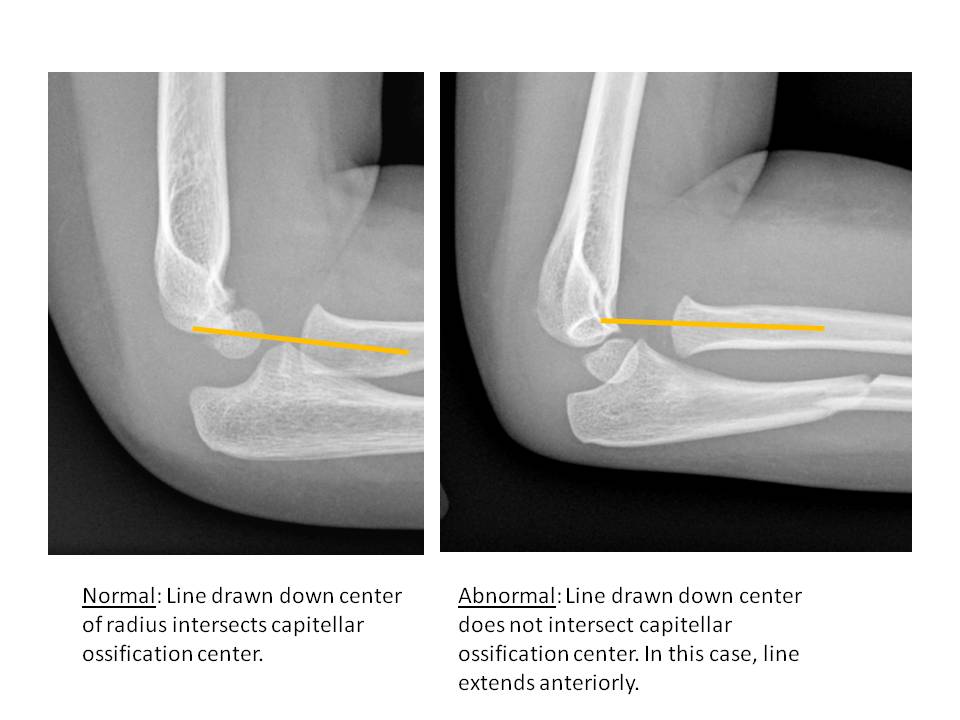

Alignment